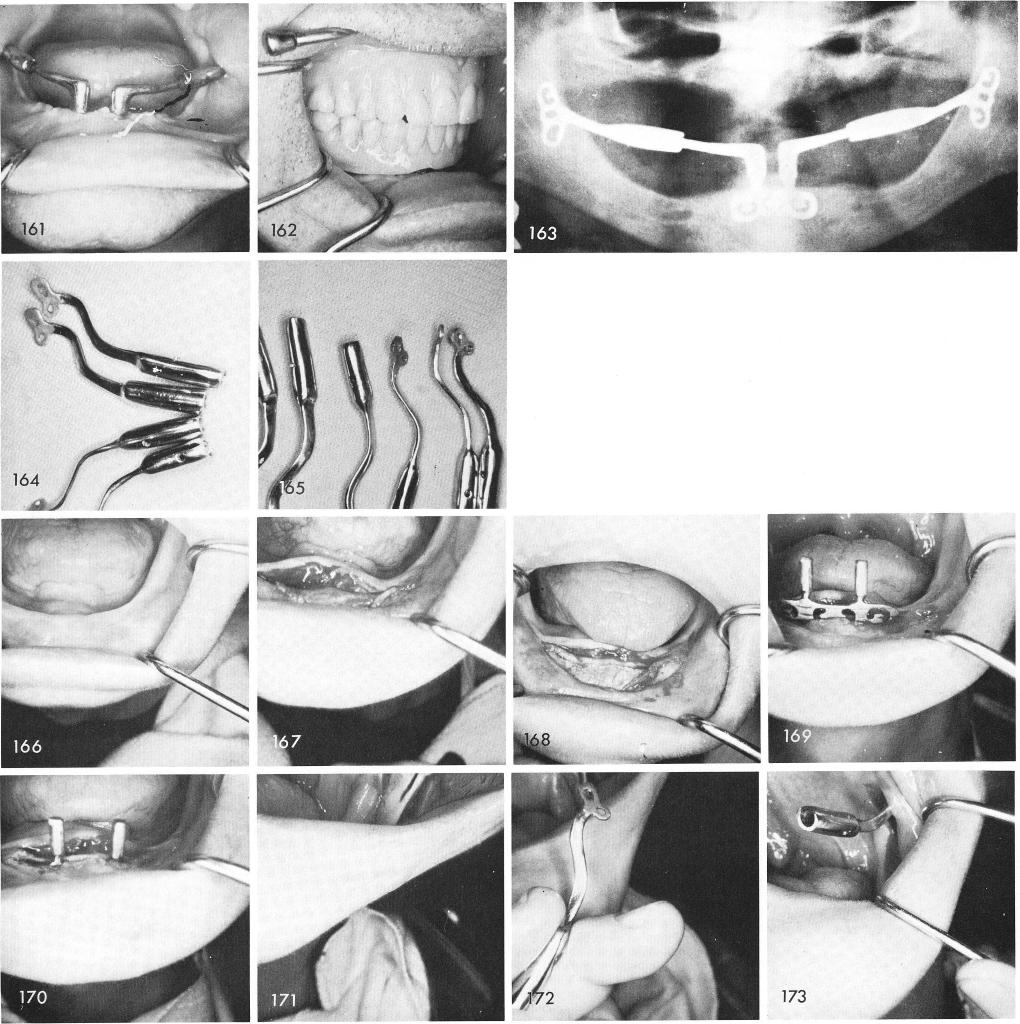

Some early improvements of the ramus implants had superior-inferior curves to eliminate prematurities with the opposing dentition and bucco-lingual curves to eliminate cross-bites, figs. 164, 165.

This next case, fig. 166, clearly demonstrates the technique which includes incising and reflecting the anterior tissue, fig. 167, making of the anterior groove, fig. 168, and fitting in the symphyseal bladevent, figs. 169, 170. The left ramus groove was made, fig. 171, and the ramus implant fitted and inserted, figs. 172, 173. The procedure was repeated on the right side, figs. 174, 175. The anterior parts were inserted and tapped downward to seat over the anterior blade

1 Superior inferior ramus implant curve eliminates occlusal prematurity